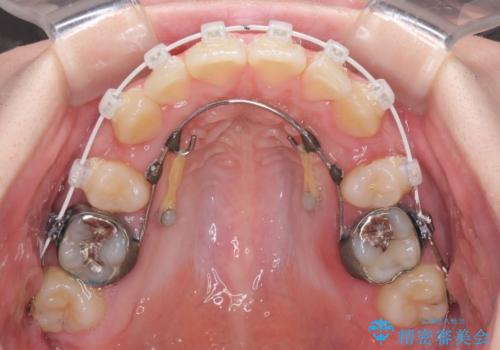

著しい八重歯を短期間で改善 ワイヤー装置による抜歯矯正

- 審美装置

- 八重歯と下顎小臼歯の欠損を気にして来院された患者様です。

下顎小臼歯の欠損により過蓋咬合となっていたため、下顎は臼歯を起こすことで咬み合わせを改善し、八重歯は第一小臼歯2本を抜歯し、補助装置を使用して速やかに改善することとしました。

著しい過蓋咬合の改善が必要であった割には、治療期間は2年強と標準的でした。

八重歯は3,4か月で速やかに改善されました。